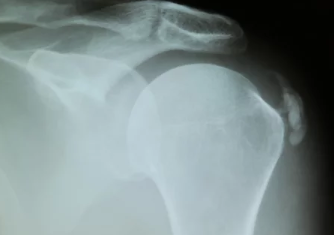

- 영상 검사:

- X-ray(엑스레이):

- 석회질의 위치와 크기를 확인하는 가장 기본적인 검사